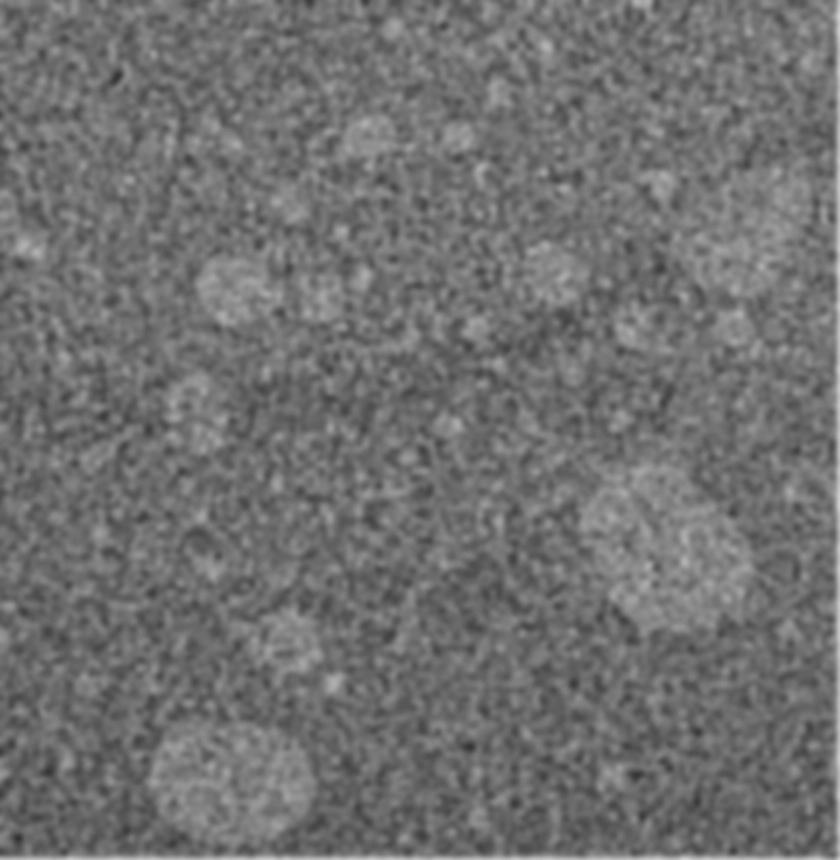

This work reports the use of X-ray microscopy (XRM) imaging to characterize the microstructure of semisolid formulations containing multiple immiscible phases. For emulsion-based semisolid formulations, the disperse phase globule size and its distribution can be critical quality attributes of the product. Optical microscopy and light diffraction techniques are traditionally used to characterize globule size distribution. These techniques are subjected to sample preparation bias and present challenges from matrix interference and data processing. XRM imaging is an emergent technique that when combined with intelligent data processing has been used to characterize microstructures of pharmaceutical dosage forms including oral solid formulations, controlled release microspheres, and lyophilized products. This work described our first attempt to use XRM imaging to characterize two complex emulsion-based semisolid formulations, a petrolatum-based ointment with a dispersed phase comprising a hydrophilic liquid, and an oil-in-water cream. This initial assessment of technology showed that microstructure details such as globule size distribution, volume fraction, spatial distribution uniformity, inter-globule spacing, and globule sphericity could be obtained and parameterized. It was concluded that XRM imaging, combined with artificial intelligence–based image processing is feasible to generate advanced characterization of semisolid formulation microstructure through 3D visualization and parameterization of globule attributes. This technique holds promise to provide significantly richer microstructure details of semisolid formulations. When fully developed and validated, it is potentially useful for quantitative comparison of microstructure equivalence of semisolid formulations.